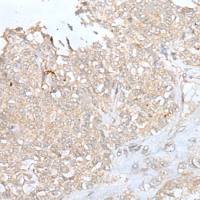

| Applications: | ELISA,WB |

| Immunogen: | SyntheticpeptideofhumanZNF365 |

| WBPositivecontrol: | Humanlivercancertissue |